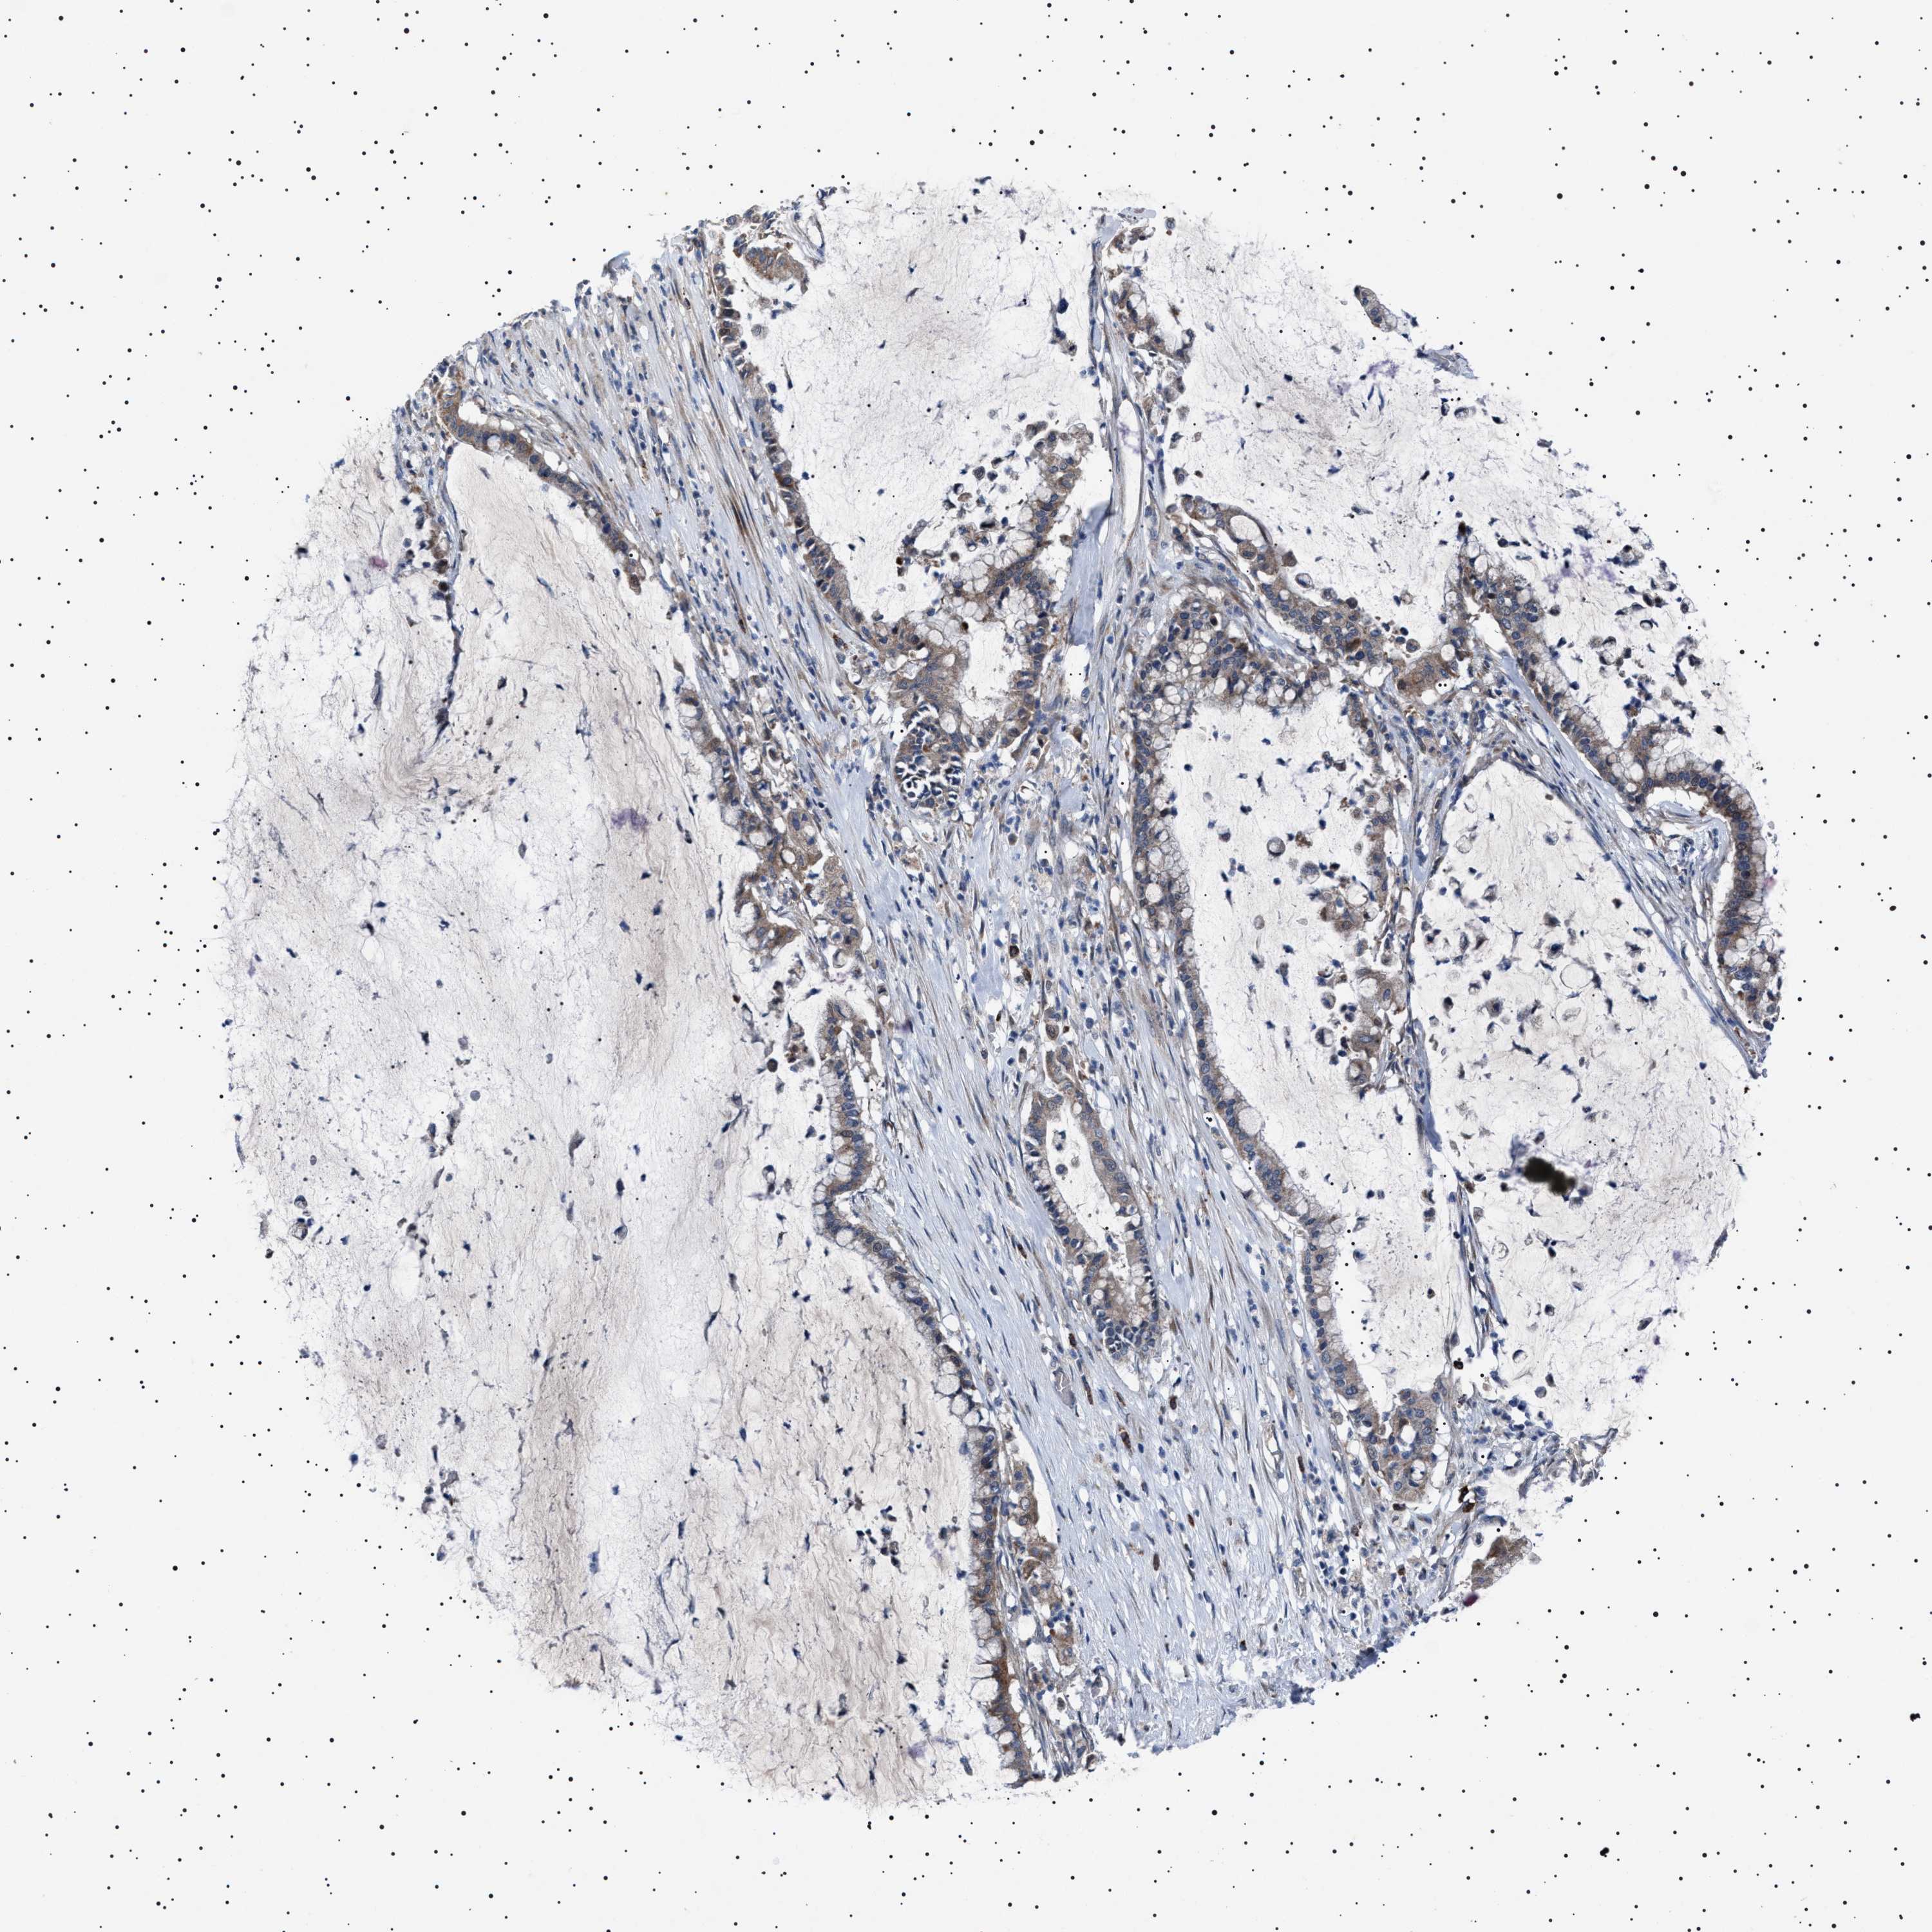

PANCREATIC CANCER - Protein expressioni

A mouse-over function shows sample information and annotation data. Click on an image to view it in a full screen mode. Samples can be filtered based on level of antibody staining by selecting one or several of the following categories: high, medium, low and not detected. The assay and annotation is described here.

Note that samples used for immunohistochemistry by the Human Protein Atlas do not correspond to samples in the TCGA dataset.

Antibody stainingi

Antibody staining in the annotated cell types in the current human tissue is reported as not detected, low, medium, or high, based on conventional immunohistochemistry profiling in selected tissues. This score is based on the combination of the staining intensity and fraction of stained cells.

Each image is clickable and will lead to virtual microscopy that enables deeper exploration of all samples and also displays staining intensity scores, fraction scores and subcellular localization as well as patient and tissue information for each sample.

Antibody HPA021223

Staining

High

Medium

Low

Not detected

Intensity

Strong

Moderate

Weak

Negative

Quantity

>75%

75%-25%

<25%

None

Location

Nuclear

Cytoplasmic/membranous

Cytoplasmic/membranous,nuclear

Adenocarcinoma, NOS